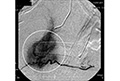

画像引用元:東京MITクリニックHP(http://www.comfort-hp.com/pages/03.html) スキルス性胃がん―【手術不能・打つ手なし】食事も通らなくなってしまったため、ステントを挿入。余命は長くて3ヶ月との診断だったが、免疫療法開始から8ヶ月でがん細胞の成長が止まり、がんとの共存状況を保つ。